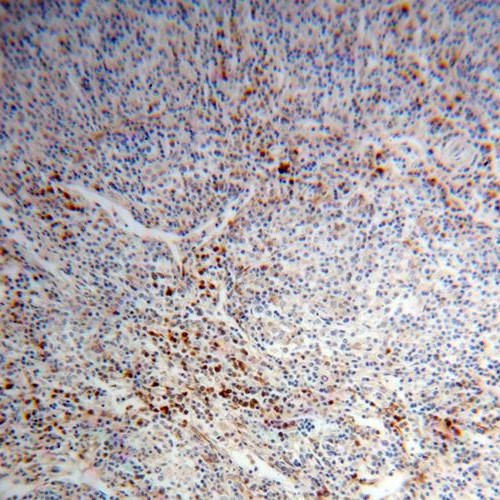

Immunohistochemistry of paraffin-embedded human lymphoma using FNab06389(PHGDH antibody) at dilution of 1:100 IP Result of anti-PHGDH (IP:FNab06389, 4ug; Detection:FNab06389 1:1000) with mouse brain tissue lysate 4000ug.